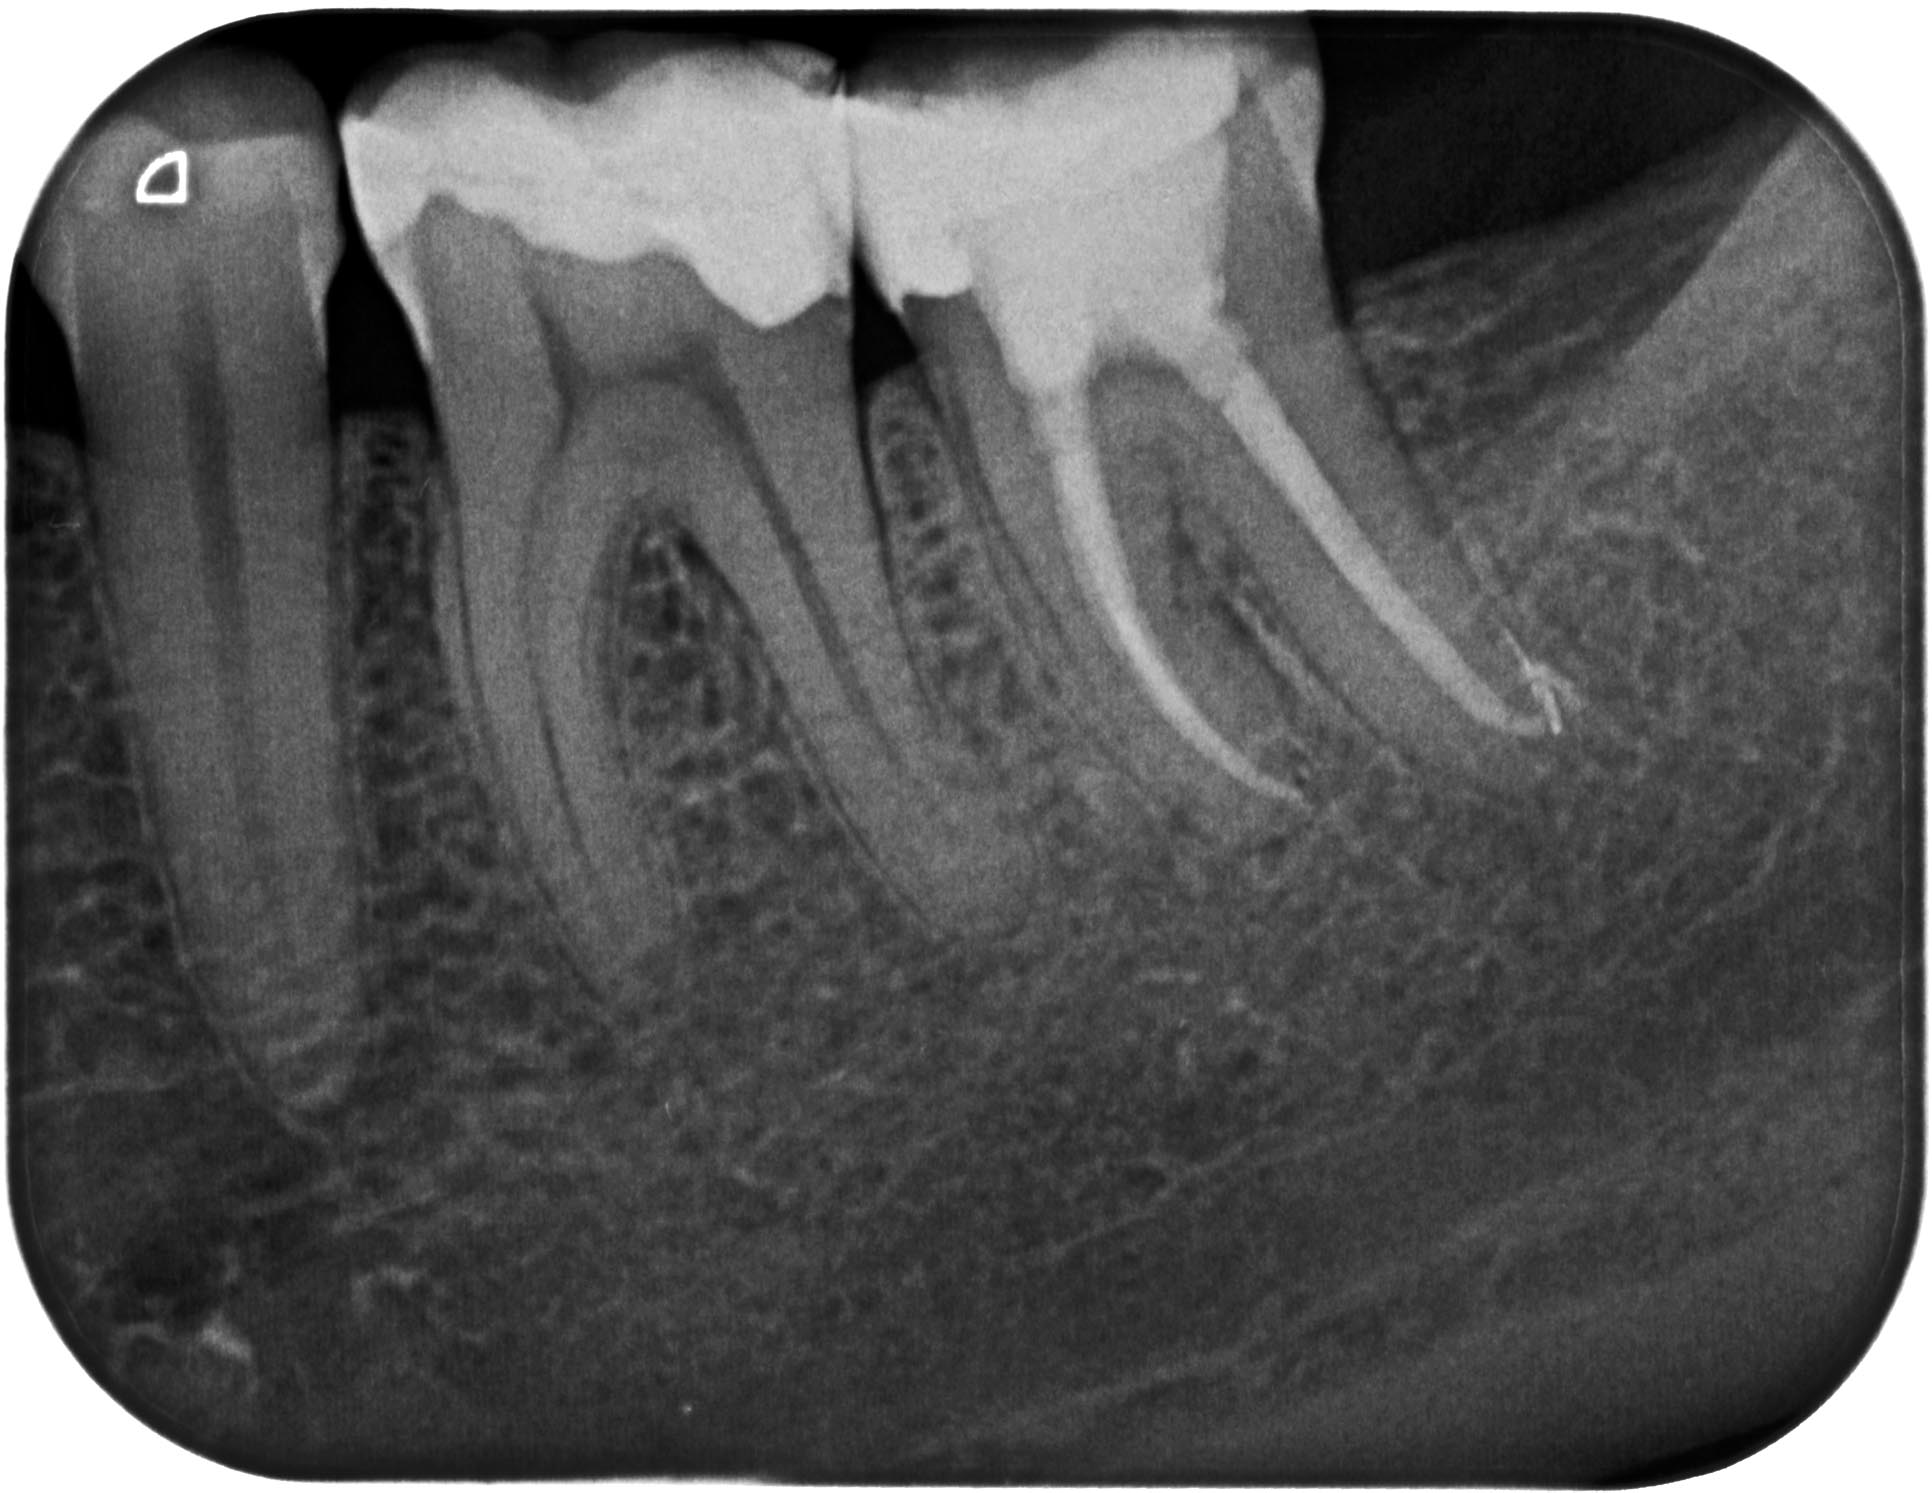

AA-1-4 Veröffentlicht 11. September 2012 am 1932 × 1493 in Recall des Tages – Zahn 37 mit apikaler Aufhellung